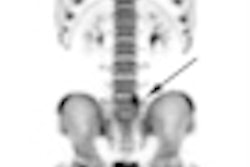

In a comparison with F-18 DOPA-PET/CT, gallium-68 (Ga-68) DOTA-NOC achieved "superior sensitivity" with neuroendocrine tumors, prompting researchers to conclude that Ga-68 DOTA-NOC could help direct more effective patient treatment.Ga-68 DOTA-NOC is a PET/CT agent that binds to the somatostatin receptor, which expresses neuroendocrine tumors, according to presenter Dr. Abhishek Kumar, a resident physician at All India Institute of Medical Sciences in New Delhi. "Since FDG-PET very often does not show uptake in neuroendocrine tumors, this new agent seems to be very promising," he added.

In the subgroup of carcinoid patients, Ga-68 DOTA-NOC achieved sensitivity of 96%, compared with F-18 DOPA's sensitivity of 71%. In the subgroup of medullary thyroid carcinoma patients, Ga-68 DOTA-NOC showed a sensitivity of 100%, compared with F-18 DOPA at 86%.

Ga-68 DOTA-NOC identified more metastatic liver, lymph node, and bone lesions in patients with carcinoids as well as medullary thyroid carcinoma. In the pheochromocytoma subgroup, all patients were positive on both of the studies.